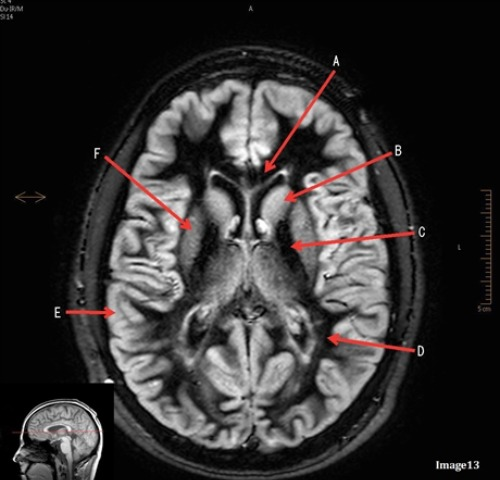

Letter B in image 13 is pointing to:

A. Splenium of the corpus callosum

B. Genu of the corpus callosum

C. Lentiform Nucleus

D. Caudate nucleus

E. Internal capsule

Letter D in Image 13 is pointing to:

A. Grey matter

B. White matter

Letter C in Image 13 is pointing to:

Letter E in Image 13 is pointing to:

Letter F in Image 13 is pointing to: